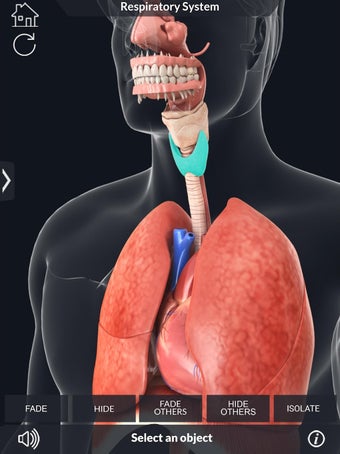

このアプリケーションは、高度にリアルな呼吸器系のモデルです。ユーザーは任意の角度および任意の平面から呼吸器系の解剖学を表示できます。ユーザーは360°回転し、ズームインおよびズームアウトして解剖学をよりよく研究することができます。ユーザーはまた、画面に描画するためのさまざまなツールを使用して写真を撮ることもできます。